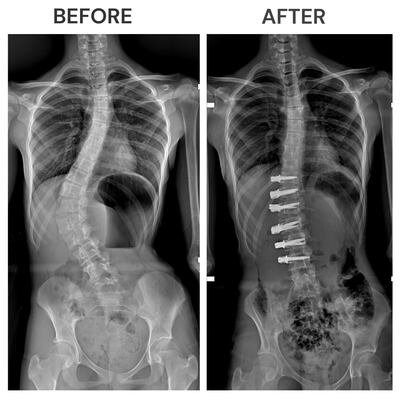

A Dubai schoolgirl born with a spinal deformity is the first in the UAE to benefit from a non-invasive corrective procedure to stop a progressive condition that would have worsened as she grew.

The Jordanian teenager was diagnosed with scoliosis in April, when her parents first noticed an unusual curve in her spine. The condition typically appears as children grow into their teens.

Due to her condition, Salma suffered a deformity of the back with a shortening of the trunk, a lower back hump, an unlevelled pelvis and back pain that stopped her playing sports and moving freely.

The innovative procedure uses a flexible cord rather than metal rods to straighten the curvature of the spine.

Usually, doctors would have to correct the condition with spinal fusion surgery by inserting metal screws and rods.

The vertebral body tethering was approved in 2019 in the US, and uses discreet incisions in the abdomen through an endoscope to fix a flexible cord to the spine.

The tether costs about $45,000 and is applied to the outside of the curve through bone screws, then tension is applied to straighten the spine.

Corrective surgery is essential in cases such as Salma’s, where patients have large curves of 45 to 65 degrees.